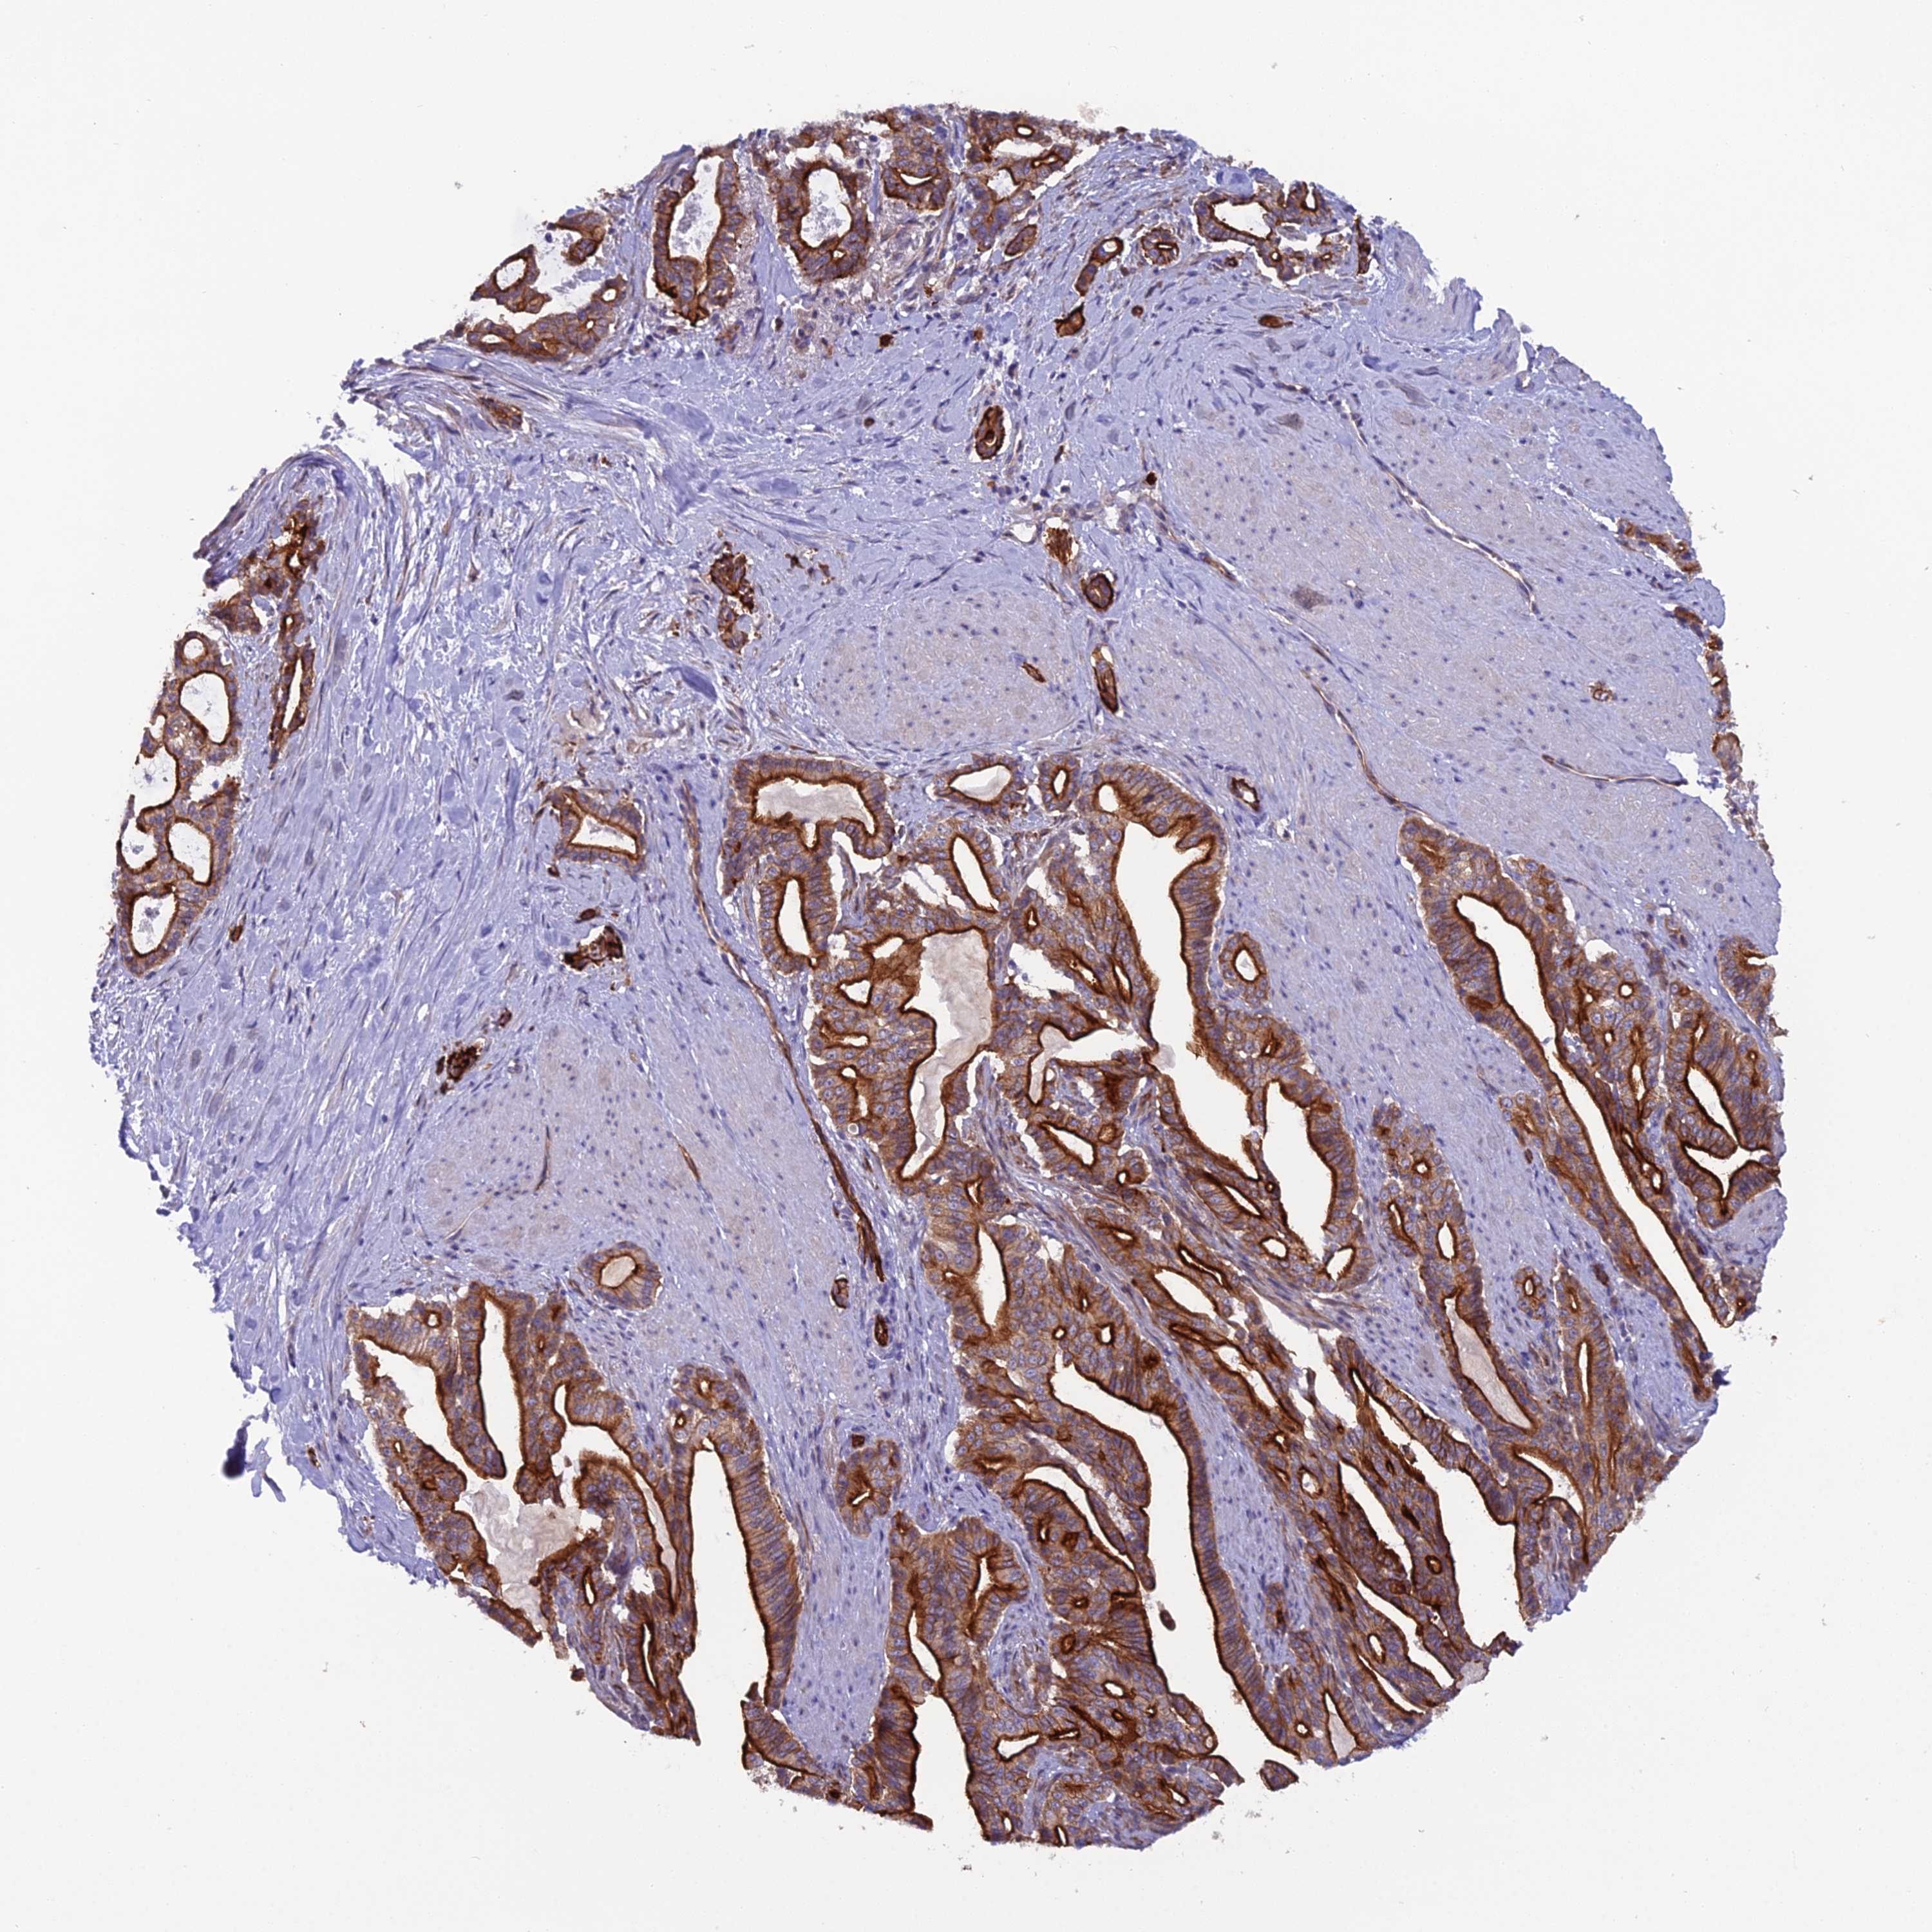

PANCREATIC CANCER - Protein expressioni

A mouse-over function shows sample information and annotation data. Click on an image to view it in a full screen mode. Samples can be filtered based on level of antibody staining by selecting one or several of the following categories: high, medium, low and not detected. The assay and annotation is described here.

Note that samples used for immunohistochemistry by the Human Protein Atlas do not correspond to samples in the TCGA dataset.

Antibody stainingi

Antibody staining in the annotated cell types in the current human tissue is reported as not detected, low, medium, or high, based on conventional immunohistochemistry profiling in selected tissues. This score is based on the combination of the staining intensity and fraction of stained cells.

Each image is clickable and will lead to virtual microscopy that enables deeper exploration of all samples and also displays staining intensity scores, fraction scores and subcellular localization as well as patient and tissue information for each sample.

Antibody HPA044633

Antibody HPA054859

Staining

High

Medium

Low

Not detected

Intensity

Strong

Moderate

Weak

Negative

Quantity

>75%

75%-25%

<25%

None

Location

Nuclear

Cytoplasmic/membranous

Cytoplasmic/membranous,nuclear

Adenocarcinoma, NOS